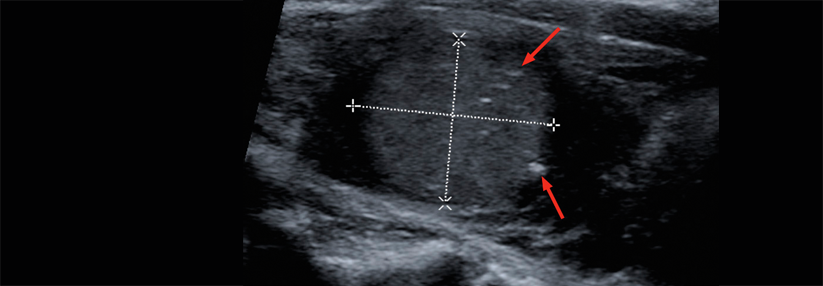

Bei fortgeschrittenen Schilddrüsenkarzinomen mit RET-Fusion oder -Mutation wird ein weiterer RET-Kinasehemmer getestet. Nun wurde eine erste Datenanalyse präsentiert.

Der RET-Kinase-Inhibitor Selpercatinib (LOXO-292) wird derzeit bei mehreren Tumoren mit Alterationen in der RET-Kinase klinisch geprüft, darunter Schilddrüsentumoren. LIBRETTO-001 ist eine globale Studie der Phase I/II, in der die Substanz in Abhängigkeit von Tumorart, RET-Veränderungen und Vortherapie in sechs Kohorten untersucht wird. Primärer Endpunkt ist die allgemeine Ansprechrate. Die Ansprechdauer, das progressionsfreie Überleben sowie das Gesamtüberleben zählen zu den sekundären Endpunkten.